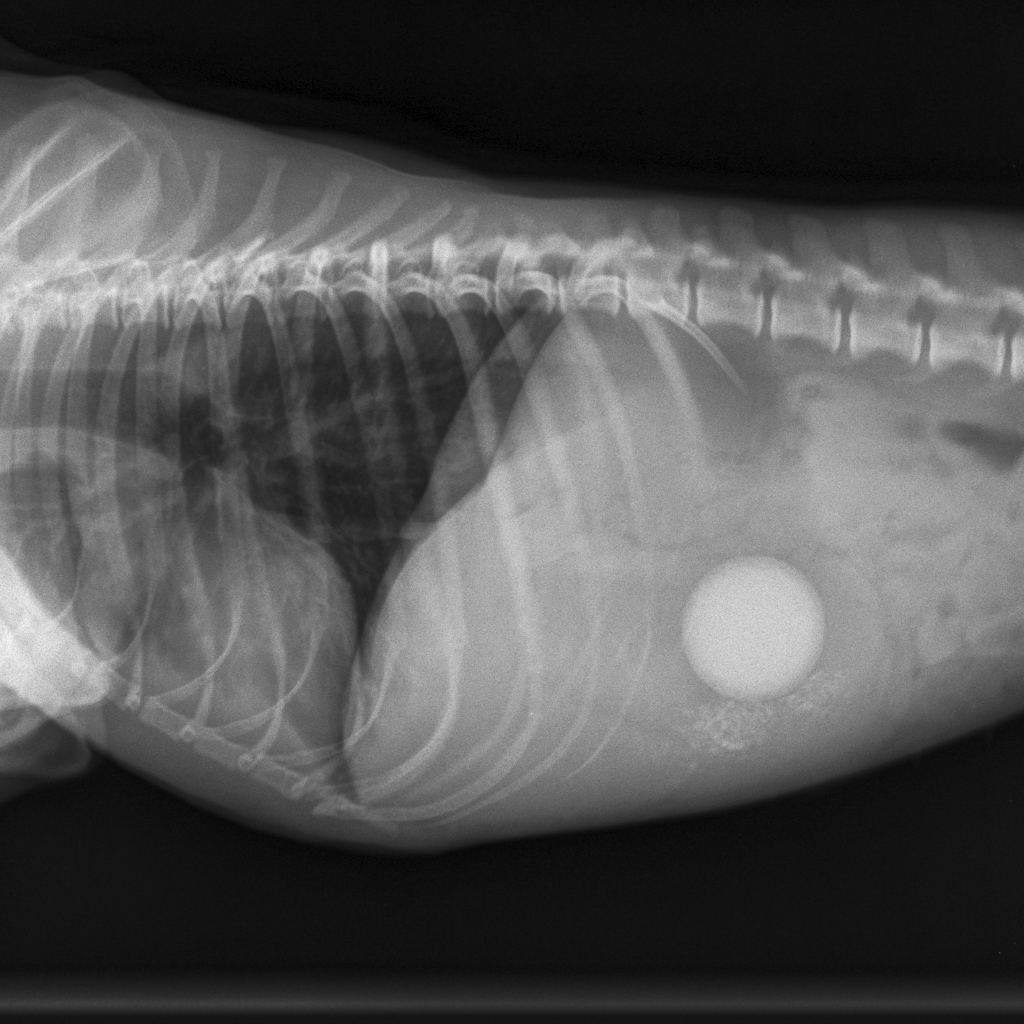

Bij het onderzoek op de praktijk blijkt Lady een erg pijnlijke buik te hebben en een hoge hartslag. Ze heeft wat verhoging en voelt zich alles behalve goed. Op de röntgenfoto is goed te zien wat lady in de weg zit.....de verloren stuiterbal is waarschijnlijk gevonden. We hebben middels een operatie de stuiterbal uit de maag verwijderd en Lady was vrijwel driect weer als nieuw! We zijn nu een dikke week verder en Lady doet alsof er nooit wat gebeurd is. Hopenlijk levert het ook een leermomentje op voor in de toekomst. Hieronder ziet u enkele foto's van Lady.

De stuiterbal is goed te zien.